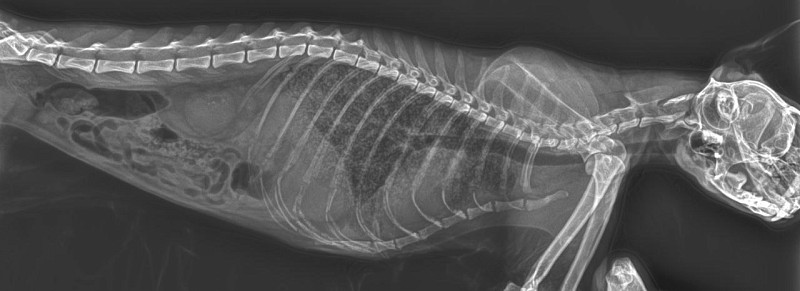

Кошка, 14,5 лет, точная порода неизвестна.

По рентгену предполагают рак легких.

Здравствуйте! по снимку выраженные диффузные изменения ткани легких, причиной тому может быть как и онкология, так и прогрессирующее хроническое заболевание бронхов/фиброзные изменения ткани легких, также есть признаки и инфильтрации легких, что характерно для развивающегося отека легких

в целом учитывая возраст, остроту клинических симптомов и картину рентгена прогноз от острожного до неблагоприятного